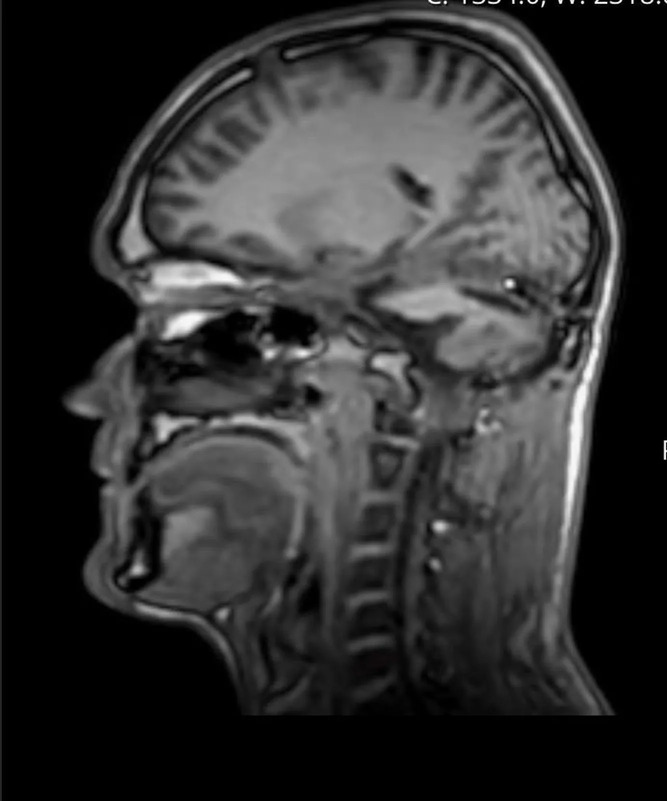

O diagnóstico final revelou um hemangioblastoma, um tumor cerebral raro e geralmente benigno, que costuma se desenvolver no cerebelo — área responsável por coordenação motora e equilíbrio.

Apesar de benigno, esse tipo de tumor pode ser extremamente perigoso quando cresce sem controle. No caso de Luke Taylor, ele atingiu o tamanho de uma bola de golfe, comprimindo estruturas vitais do cérebro.

O quadro se agravou em dois mil e vinte e cinco, quando Luke Taylor decidiu exigir uma ressonância magnética. O exame revelou a gravidade da situação. Segundo o próprio paciente, os médicos foram diretos: sem cirurgia imediata, ele poderia ter apenas “dias de vida”.